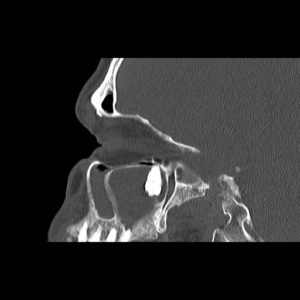

Ekstrakcja, czyli inaczej usuwanie zębów, to jeden z podstawowych zabiegów w zakresie chirurgii stomatologicznej. Wykonywany jest w znieczuleniu miejscowym – prawidłowo podane uwalnia od bólu w stu procentach. Od każdej reguły zdarzają się jednak wyjątki. Oto właśnie taki. Prawa górna ósemka znajduje się pod dnem oczodołu, w świetle zatoki szczękowej (przy okazji zacienienie widoczne na zdjęciach może świadczyć o jej przewlekłym zapaleniu). W takim przypadku o „miejscówce” w ogóle nie było mowy. Żaden chirurg nie zgodziłby się na usunięcie tej ósemki w znieczuleniu miejscowym. Pacjent został przyjęty na Oddział Chirurgii Szczękowo-Twarzowej Uniwersyteckiego Szpitala Klinicznego w Opolu i tam, w warunkach bloku operacyjnego, został zoperowany w znieczuleniu ogólnym.